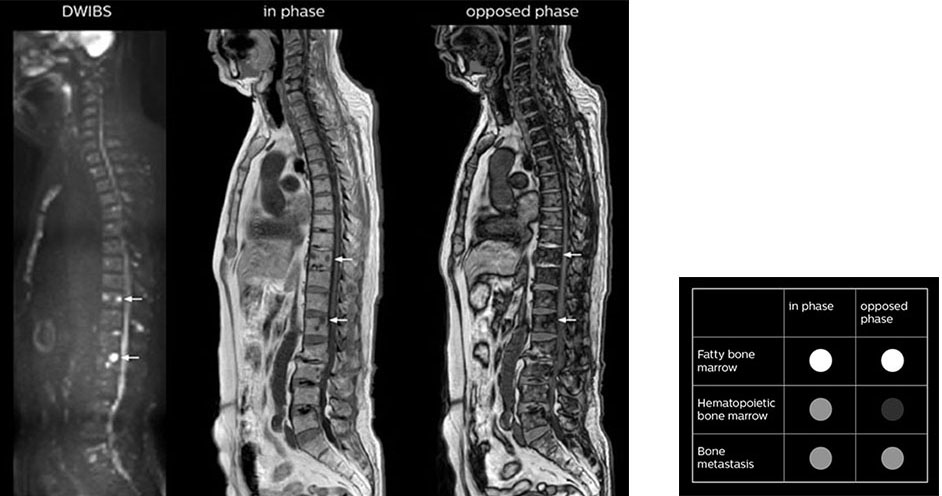

“In-phase and out-phase sagittal T1-weighted FFE images help us to visualize and further characterize bone lesions such as metastasis and bone-marrow hyperplasia that have high signal on DWI. These images are also used throughout radiotherapy, to monitor changes in the fatty bone marrow.”

“The mDIXON fat images can help us to differentiate fatty bone marrow from bone lesions. This is especially useful in elderly people, who tend to have fattier bone marrow. The water images provide a high signal-to-noise ratio in the intestinal canal, which is valuable for visualizing lesions in the colon,” he says.

“mDIXON FFE allows us to quickly get information we need to assess the presence of fat. That gives us more information when we need to diagnose bone lesions, and when we are asked to judge fat-containing lesions such as hepatocellular or renal carcinoma,” Dr. Nobusawa says.

Kawasaki Sawai Hospital’s whole body protocol also includes an mDIXON FFE sequence. Because mDIXON provides images for four contrast types – water only, fat only, in-phase and out-of-phase – from a single acquisition, it is useful in many ways.